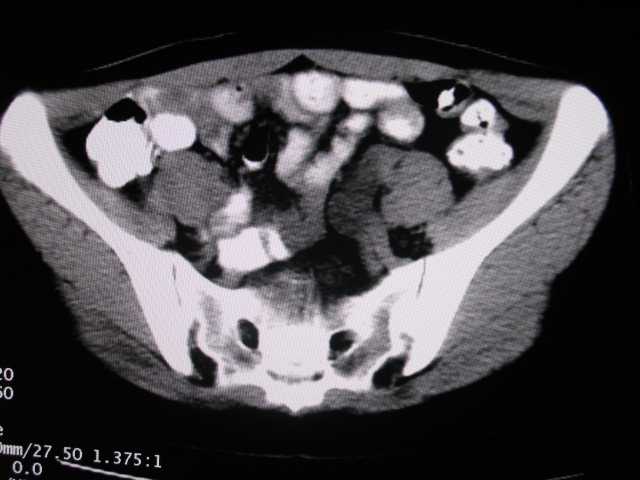

女,28岁,自觉腹部包块一年余

考虑左侧双肾盂双输尿管畸形,其中一输尿管末端梗阻(不排除异位开口可能)并相应之肾盂及输尿管明显扩张积水。

左双肾盂输尿管畸形.其一输尿管远端输尿管囊肿引起一肾盂输尿管积水.

左侧重复肾、双输尿管畸形。重复肾一般上位肾发育不良,易合并积水。

考虑左侧双肾盂双输尿管畸形,其中一输尿管末端梗阻(不排除异位开口可能,不知病人有无不自觉溢尿,有可能开口于阴道或宫颈,也可下端为盲端)并相应之肾盂及输尿管明显扩张积水。

术后证实是左侧双肾盂双输尿管畸形,巨输尿管巨肾盂症